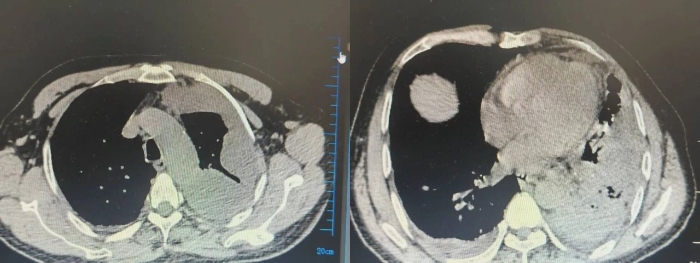

術(shù)前CT影像

患者入院時(shí),初步診斷為肺膿腫合并膿毒血癥、膿胸,出現(xiàn)高熱癥狀,心率偏高,且氣道內(nèi)咳出較多膿痰。呼吸與危重癥醫(yī)學(xué)科立即成立呼吸治療搶救組,給予床旁支氣管鏡下吸痰及抗感染、化痰、補(bǔ)液、營(yíng)養(yǎng)支持等治療,患者病情暫時(shí)穩(wěn)定。